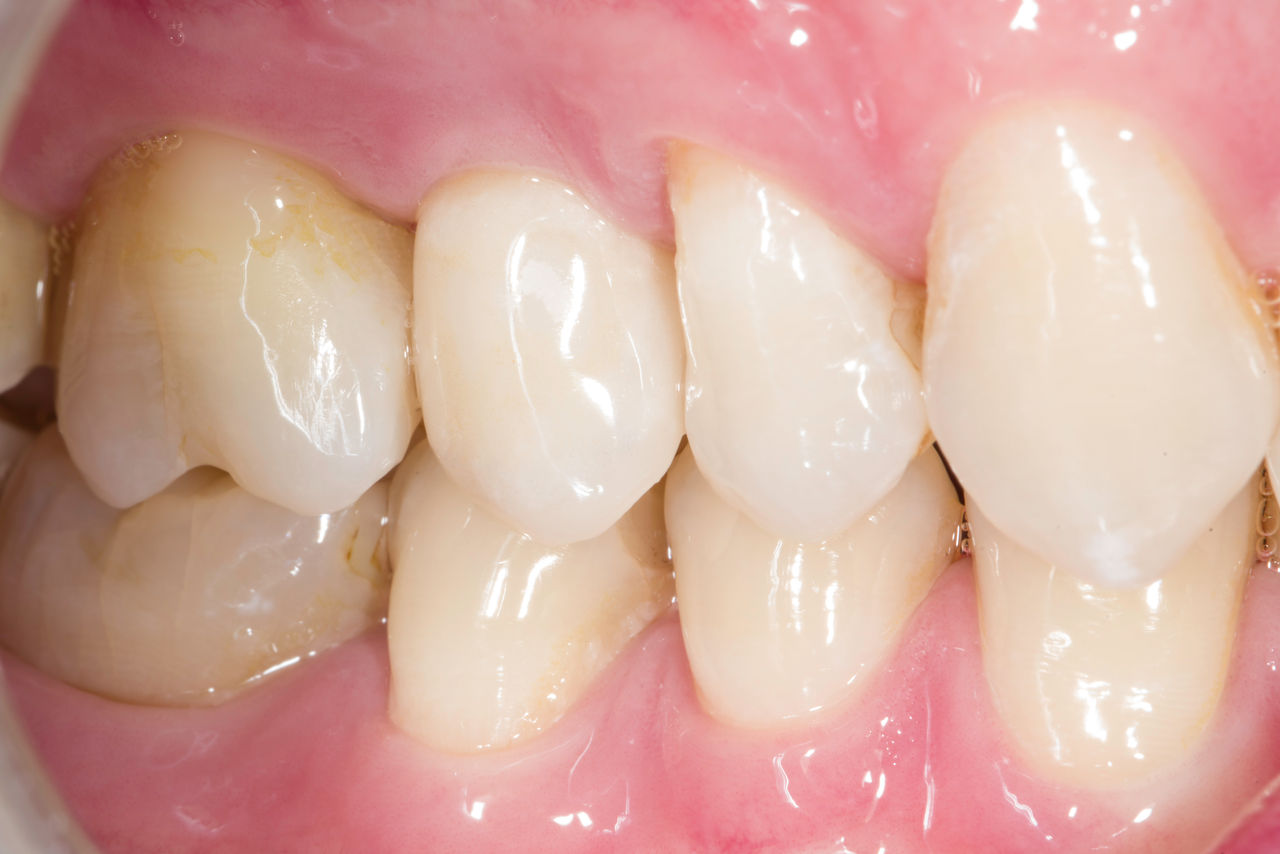

Antes: Corona de cerámica y metal fracturada en el diente 14, que había sido tratada con endodoncia.

Después: Corona de zirconia completa translúcida para un resultado estético con máxima resistencia y retención de forma.